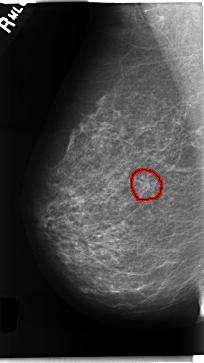

C_0230_1.RIGHT_MLO

FILE: C_0230_1.RIGHT_MLO.OVERLAY

TOTAL_ABNORMALITIES 1

ABNORMALITY 1

LESION_TYPE MASS SHAPE ARCHITECTURAL_DISTORTION MARGINS ILL_DEFINED

ASSESSMENT 5

SUBTLETY 4

PATHOLOGY MALIGNANT

TOTAL_OUTLINES 1

BOUNDARY